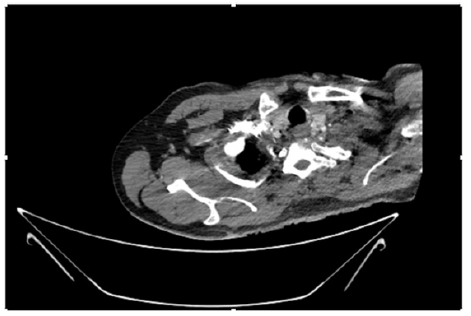

55-years-old chronic smoker had acute, severe pain in the right upper limb for one week; it was cold upto mid arm with skin discoloration. He also noticed numbness and weakness of movement of elbow joint. He underwent below elbow amputation in February 2023 for acute ischemia of left upper limb. He was a current chronic smoker; 15 pack year. General condition was weak; temperature was normal; blood pressure was 100/60mmHg; heart rate was 92/minutes with sinus rhythm; SpO2 was 97% on air; heart was normal. In lower extremities, all peripheral pulses were intact. Local Examination of right upper limb revealed as follows: tenderness; coldness; discoloration; decreased motor function and sensory modalities. Axillary, brachial and radial pulses were not palpable. Hand-held Doppler failed to detect any signal in arterial system; therefore, we arranged for emergency embolectomy. complete occlusion of right upper limb arterial system Full blood count showed high hemoglobin (14.6gm%); normal total WBC and platelet count. Coagulation profile was normal. Parenteral unfractionated heparin, antibiotics, tramadol, proton-pump inhibitors, anti-platelets and HMG CoA reductase inhibitors were given. Doppler ultrasound demonstrated complete occlusion of right upper limb arterial system. CT Angiogram illustrated occlusion of subclavian artery downwards on both sides. Figures 1-14 shows complete occlusion of right subclavian artery without collaterals. On Day ‘2’ of admission, the patient passed black tarry stool for 3 times. However, the vital signs were stable; blood pressure was 100/60mmHg; heart rate was 92/min; SpO2 was 97% on air; the abdomen was soft and not tender. Above elbow amputation was done on Day ‘2’ of admission. Intra-operative findings were as follows: (1) no active bleeding at brachial artery; (2) thrombosis along brachial artery; (3) muscle color and consistency were not healthy.

Figure 4: CT Angiogram at neck showing normal brachio-cephalic trunk, common carotid artery, and narrow right subclavian artery.

Figure 5: CT Angiogram at neck showing normal brachio-cephalic trunk, common carotid artery, and narrow right subclavian artery.

Figure 6: CT Angiogram at neck showing brachio-cephalic trunk, common carotid artery and narrow right subclavian artery.

Figure 7: CT Angiogram at neck showing brachio-cephalic trunk, common carotid artery and narrow right subclavian artery.